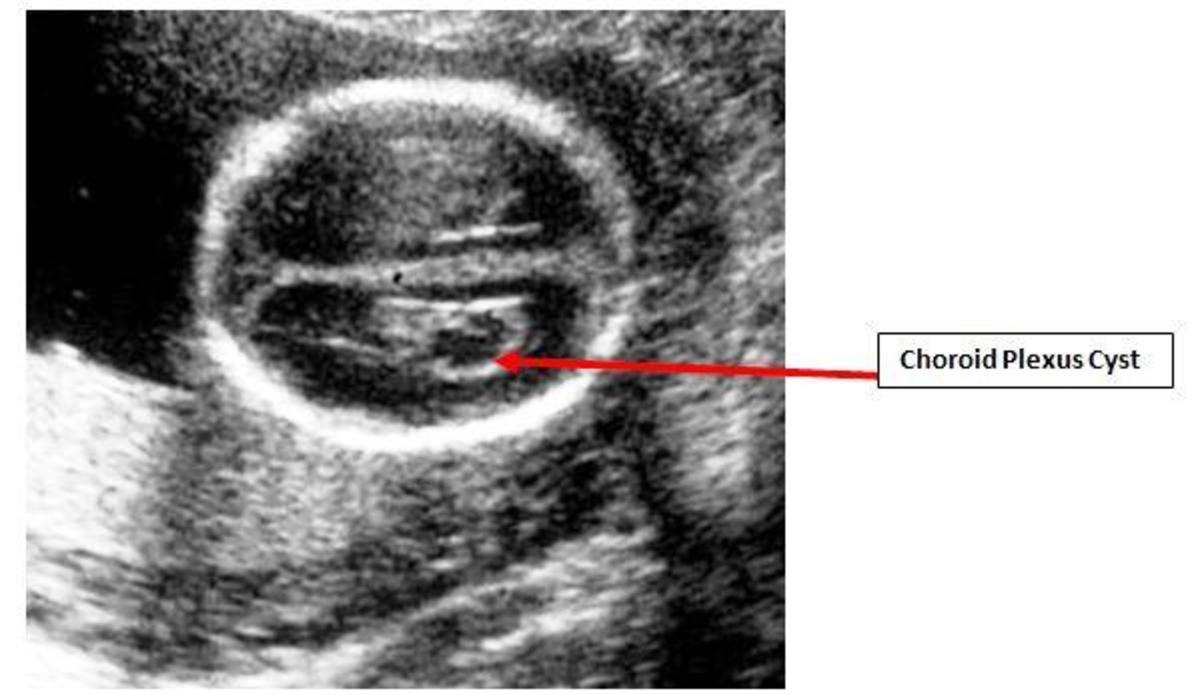

But it is necessary to take into account that the cyst can develop further, and after a time the. Web brain cysts are caused by the building up of fluid in an area of the brain. It’s estimated that choroid plexus cysts happen in about 2% of.

Web based on the measurement of cerebrospinal fluid in the brain, as well as the size of a baby's ventricles, an arachnoid cyst may be suspected. More than 90% resolve by 26 weeks. 1 in 50 fetuses at 20 weeks’ gestation.

Arachnoid cysts are the most common type of brain cyst. A baby born with a cystic. Many brain cysts form during the first few weeks when a baby is growing in the womb.

Brain cysts can form during the first few weeks when a baby is growing in the womb. Web in most cases the cyst does not grow into the ventricles of the brain. Web arachnoid cysts are the most common type of brain cyst, and can occur anywhere in the brain but most commonly in the temporal fossa or the posterior fossa.